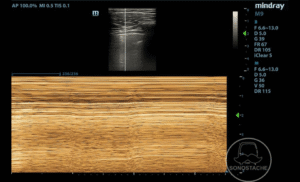

Case 2 – Pneumothorax